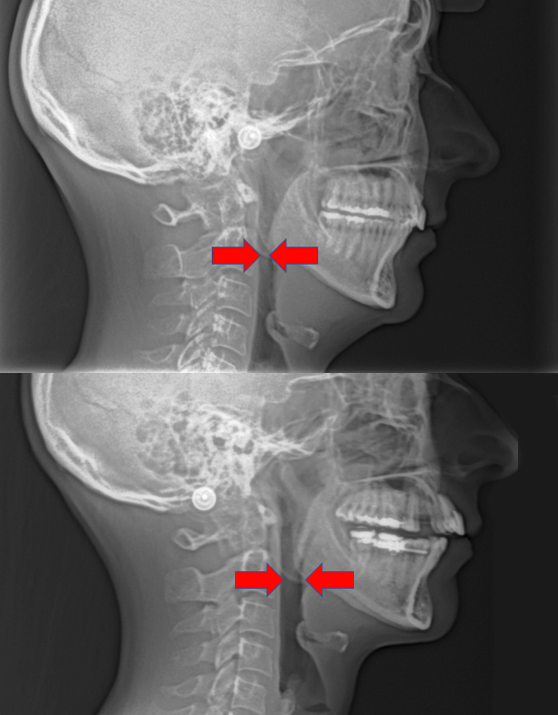

The upper arch (maxilla bone) is one of the most important bones in the body as it determines the position of the lower jaw, which in turn may affect the airway and the TMJ joints.

When your upper jaw expands during this treatment process, it can effectively realign your lower jaw, helping to relieve TMD pain, improve breathing, stop snoring and eliminate sleep apnea, without surgery.To accomplish this, we provide expansion appliances that are custom fitted to you. The type of appliance Dr. Tanner recommends will depend on your unique circumstances. Each person’s background, health history, symptoms, and facial development is taken into consideration. Once all the pieces are understood, only then can he provide a treatment plan that best suits your individual needs and concerns.The end result is an expanded upper jaw both towards the front and the sides. The jaw will be able to accommodate all permanent teeth to erupt in the correct position and may include wisdom teeth, if the conditions are right. The lower jaw is able to move forward to occlude into the ideal bite in harmony with the TMJ joints and the facial muscles. The enlarged space allows room for crowded teeth to be aligned, without extraction of any teeth. This ideal space also allows the tongue to position itself correctly against the roof of the mouth, opening up good airways at the back of the throat and inside the nose. The results are an enlarged oral cavity and airway for proper nose breathing day and night.

BEFORE

AFTER